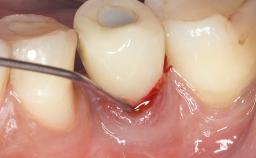

Occlusal Load—a Factor for Implant Failure?

In this case, Nicola Zitzmann describes the sudden loss of a previously well-osseointegrated implant that had been in healthy function for 5 years. The case includes recommendations for occlusion and function of implant restorations. A 74-year-old patient had received implant-fixed dental prostheses in the maxilla in 2008, and in the right mandible three years later. His tooth loss was mainly related to recurrent caries associated with hyposalivation as a potential side effect of his cholesterol-lowering medication.